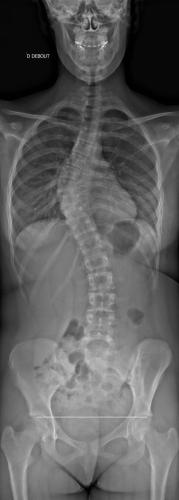

Images de scolioses opérées 16 janvier 202418 janvier 2023 par Damien Scoliose Thoracique 2 Scoliose thoracique Droite - cliché pré-opératoire de Face Scoliose thoracique Droite - cliché pré-opératoire de Profil Scoliose thoracique Droite - cliché post-opératoire de Face Scoliose thoracique Droite - cliché post-opératoire de Profil